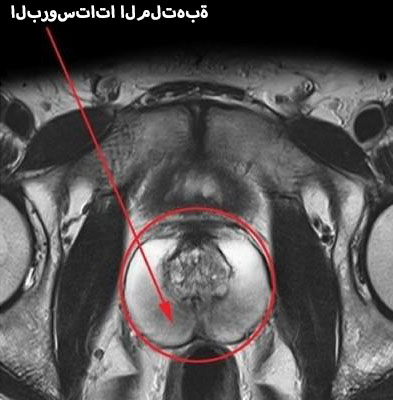

image

البروستاتا الطبيعية والملتهبة